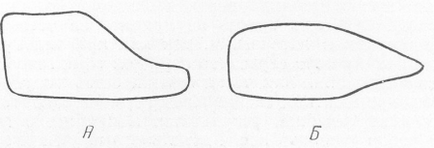

Deformarea corpului uneia dintre vertebrele lombare superioare în proiecția laterală, extrem de tipică pentru osteochondrodystrofia și gargoilismul - angularea coloanei vertebrale. Tip de deformare conform Pfoundler-Hurler ("limbă inferioară"). Boala principală este complicată de rahitismul tratat cu succes; benzi de MS. Structura vertebrelor este defectuoasă, grosieră. Contururile corpurilor vertebrale sunt subliniate, dar pierd un curs neted, devin inegale. Cel mai caracteristic osteohondrodistrofii manifestare radiografice este definită, cu nimic pentru a se amestecă și diagnostically importante imagini deformare contur pe latura (fig. 281-283). Preocuparea este că una sau două vertebre, și anume, trecerea la lombare toracice - de obicei, I sau II la nivelul vertebrelor lombare, și vertebră toracică, uneori, XII, partea din față prezintă un defect. Jumătatea superioară a hipoplazica vertebrale, jumătatea inferioară se reliefează ca prova navei, și, prin urmare, în trepte din față a corpului coraco sau deformate, este nevoie de o conic, a subliniat forma anteriorly verhneperedny de circuit devine scara, terrasopodobnym.

Cocoșul cu constricția proceselor spinoase în regiunea lombar-toracică. Deformarea tipică a corpului vertebrelor toracice XII. Tip de deformare de către Morkio-Brailsford ("limba centrală"). Spondiloza secundară semnificativă secundară deformantă. Această așa-numitul prim tip tulpină - tip Pfaundlera-Hurler (M. Pfaundler, Gertrude Hurler), "limba de jos", de multe ori observat la gargoylizme (a se vedea mai jos.) (Figurile 281, 283, A.). In alte cazuri, corpul vertebral este întins scurtat și ascuțit în mijloc, la o distanță egală față superioară și inferioară zonelor, așa-numita tulpina tip doua - Morquio-Breylsfloda „limbă centrală“ (Fig 282, 283, B.). În unele cazuri, această caracteristică deosebit de calitativă de deformare a osteochondrodystrofei apare în organele nu ale unuia, ci mai multe vertebre adiacente. Această dimensiune redusă a vertebrelor nedevelopate, atunci când se alunecă din rândul drept înapoi, iar vertebrele toracice deasupra ei se atarna. Acesta este modul în care se dezvoltă deformarea coloanei vertebrale, kyfozei sau angulației, care este specifică osteochondrodystrofiei, adică îndoială unghiulară, o cocoșă. La distorsiune unghiulare foarte ascuțite se pot produce comprimarea suprafeței posterioare a corpului vertebrei deplasată a măduvei spinării, însoțite de consecințele neurologice corespunzătoare secundare severe, amenințătoare de viață. În craniu nu există nimic radiologic despre nimic. Se pare că este relativ mare. Zona șei turcești este normală. In cazurile severe, poate exista un anumit grad konveksobazii, coloana vertebrală împinge în sus de bază a craniului, care exacerbează în continuare scurtarea gâtului și apropierea craniului la cuștii toracice. Ar trebui, de asemenea, să acorde atenție cariilor dentare relativ frecvente dezvoltate.

Fig. 283. Schema tipică a deformării osteochondrozei vertebrelor lombare toracice XII, I sau II, observată mai des cu gargoyleismul. Tip A conform lui Pfoundler - Hurler, "limbă inferioară"; tip B de Morkio-Brailsford, "limba centrală". La primul tip există o pantă ușoară a platformei superioare, cu al doilea tip - două rampe, zonele superioare și inferioare ale corpului vertebrelor afectate.